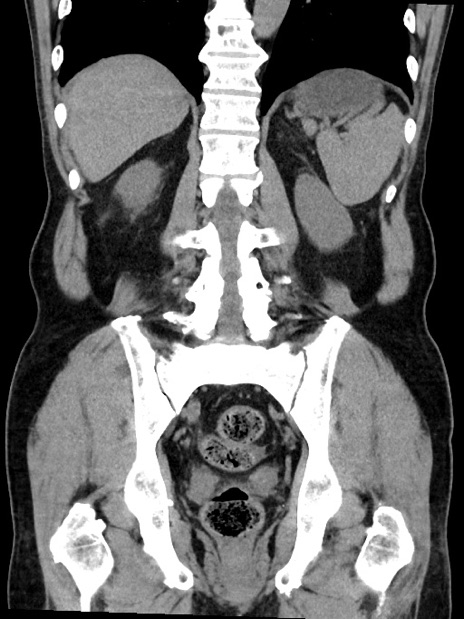

症例35(冠状断像)

【症例】70歳代 男性

【主訴】腹部膨満、嘔吐

【現病歴】昨日より腹部膨満感出現。本日増悪し、仙痛出現。嘔吐あり、受診。

【既往歴】糖尿病、胆摘後

【身体所見】BP 149/80mmHg、HR 74/min、BT 35.9℃、腹部:膨満、軟、圧痛なし。腸雑音減弱あり。上腹部正中切開瘢痕あり。

【データ】WBC 13500、CRP 1.72